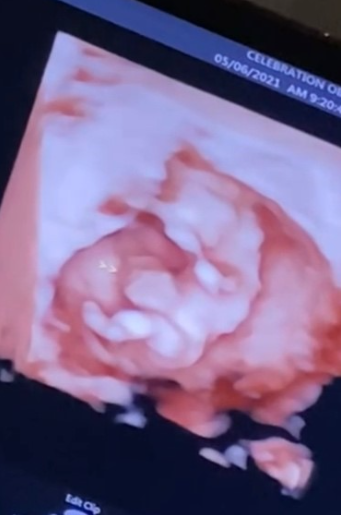

May 6th, 2021 was the day I found out about my daughter’s omphalocele. It was my first ultrasound appointment; I was 11 weeks pregnant. Everyone greeted me with big warm smiles and made friendly conversation up until my OBGYN started conducting the ultrasound. It got so quiet and I felt the room get cold, I knew something was wrong. I was told about her omphalocele, a rare condition where the abdominal organs get stuck in the umbilical cord forming a sac outside of the belly through the belly button. Still, no one had much knowledge at all about this defect.